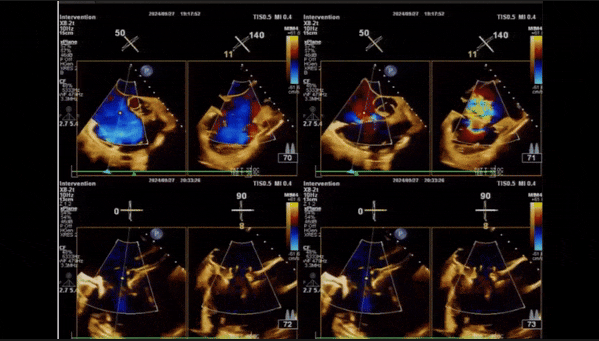

術(shù)后即刻返流

術(shù)后即刻返流三維

術(shù)后三維超聲

術(shù)后即刻經(jīng)食道超聲可見,三尖瓣假體瓣膜位置合適,牛心包瓣葉運動狀態(tài)良好,開閉正常,瓣周及瓣葉對合緣處未見明顯返流,心電圖及心包狀態(tài)較術(shù)前無明顯變化。

術(shù)前術(shù)后返流情況對比